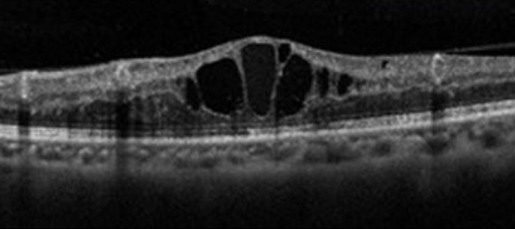

視力が低下した場合は、主に黄斑浮腫が生じていることが多いです。黄斑浮腫を改善する治療をします。

01.薬物注射

静脈からの血液や水分のもれを抑制する薬を眼に注射します。

詳細は黄斑疾患の抗VEGF注射をご覧ください。

ステロイド剤は、炎症を抑えたり血管から水分が漏れ出てきやすい状態を改善します。

眼の外側に注射します。